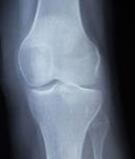

老年人的滑膜炎大多发生在骨关节炎的基础上,或者就是在关节老化的基础上,表现出的症状就是滑膜肿胀、积液、疼痛、活动受限等,但是很多病症一般是发生在长途跋涉、爬山、体育运动等这些体育锻炼之后才有所表现的。比如关节疼痛,特别是坐久了一站立起来开始走路就感觉特别的疼痛,但是走一段路程之后就会好转,大家称这种疼痛为启动痛,像这类病人在做X射线检查时,会发现关节间隙变窄了,有骨质增生的迹象等。

除了上述所提到的滑膜炎症状之外,还有一些特殊类型的滑膜炎,比如色素沉着绒毛结节性滑膜炎,它最明显的症状就是反复发生关节肿痛,这种滑膜炎的关节液大多是血性的,病史也比较长。病变比较严重的会侵蚀到软骨和骨子里,这种类型的滑膜炎患者只有通过X射线检查或者是通过核磁共振才可以检查出来。